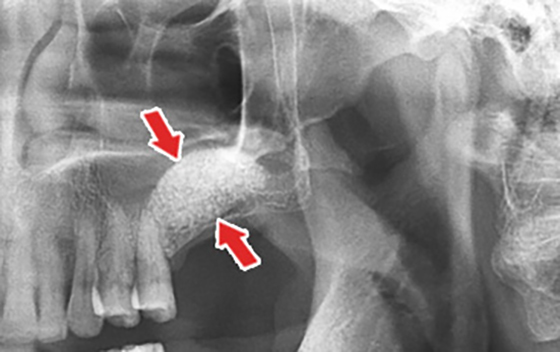

»ó¾Çµ¿ °Å»ó¼úÀº À­ÅÎ ¾î±Ý´Ï¿¡ ÀÓÇöõÆ®¸¦ ½Ä¸³ÇØ¾ß Çϴµ¥ »À°¡ ºÎÁ·ÇÑ °æ¿ì¿¡ ½ÃÇàÇÏ´Â ½Ã¼ú¹ýÀÔ´Ï´Ù. À§ÅÎ ¾î±Ý´ÏÀÇ »óºÎ¿¡´Â »À ³»ºÎ¿¡ »ó¾Çµ¿À̶ó´Â ºó °ø°£ÀÌ Àִµ¥ À§ÅÎ ¾î±Ý´ÏÀÇ ÀÓÇöõÆ® ½Ã¼ú½Ã »À°¡ ºÎÁ·ÇÑ °æ¿ì¿¡´Â »ÀÀ̽ÄÀ» À§Çؼ­ »ó¾Çµ¿À» ¾à°£ µé¾î¿Ã¸± Çʿ䰡 ÀÖ½À´Ï´Ù. ÀÌ ½Ã¼úÀ» »ó¾Çµ¿ °Å»ó¼úÀ̶ó°í ÇÕ´Ï´Ù.

»ó¾Çµ¿ °Å»ó¼úÀº 3Â÷¿øCT³ª ÆÄ³ë¶ó¸¶ ÃÔ¿µÀ» ÅëÇÏ¿© »ó¾Çµ¿ÀÇ ÇüÅÂ¿Í Å©±â, À­ÅλÀÀÇ °ñµÎ²²¿Í °ñÁú Á¤µµµîÀ» ÆÄ¾ÇÇÏ¿© ²À ÇÊ¿äÇÑ È¯ÀÚ¿¡°Ô¸¸ ½Ã¼úÇÕ´Ï´Ù.